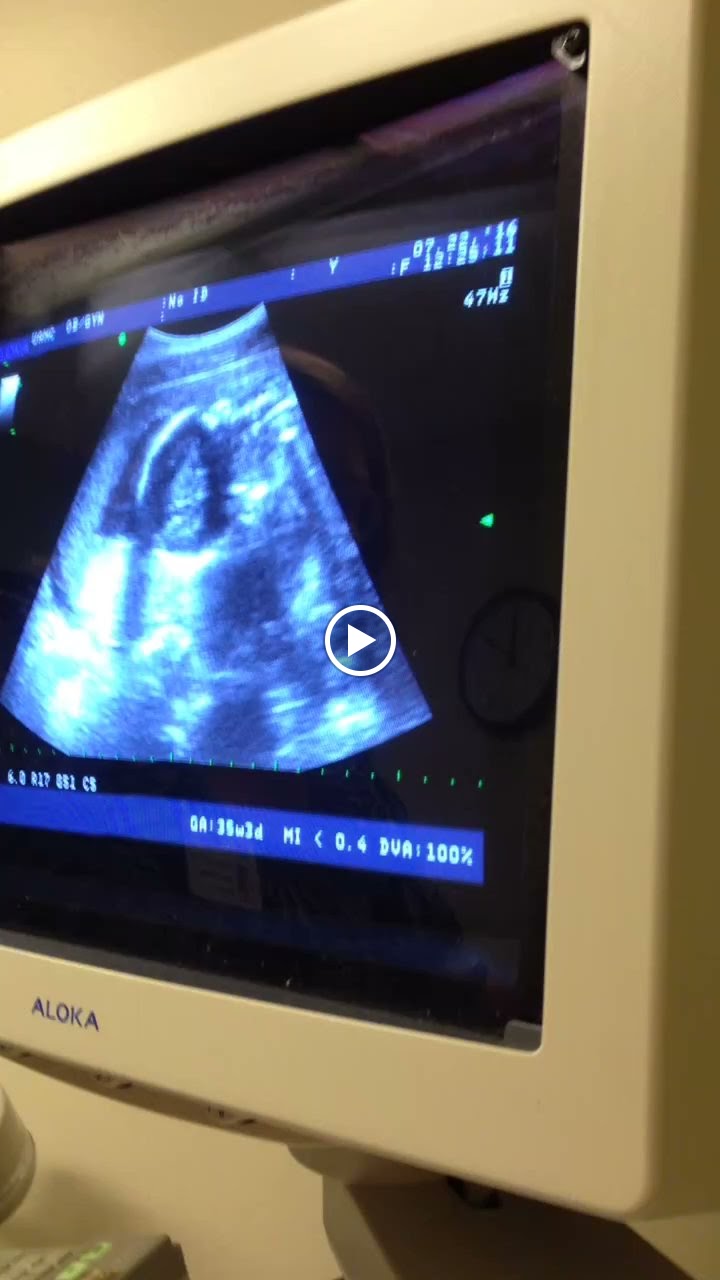

| Our 23-week ultrasound 🙂 Hey girl! Nice spine. |

On a lighter, brighter note, I’m still very pregnant! 23 weeks to be (semi) exact. Our ultrasound tech told us at 18 weeks that our girl was measuring like a 20-week-old…but then again, she’s our offspring so of course she’s enormous. But we adjusted the due date in our heads to November 12 after our technician said she’d definitely be arriving well before November 25. But we asked our OB two days ago and she said, “Nah, we’ll keep the due date November 25.” hah. So we’re going to make up a due date. Matt and I, with all of our prenatal expertise, have declared November 20 the new due date.